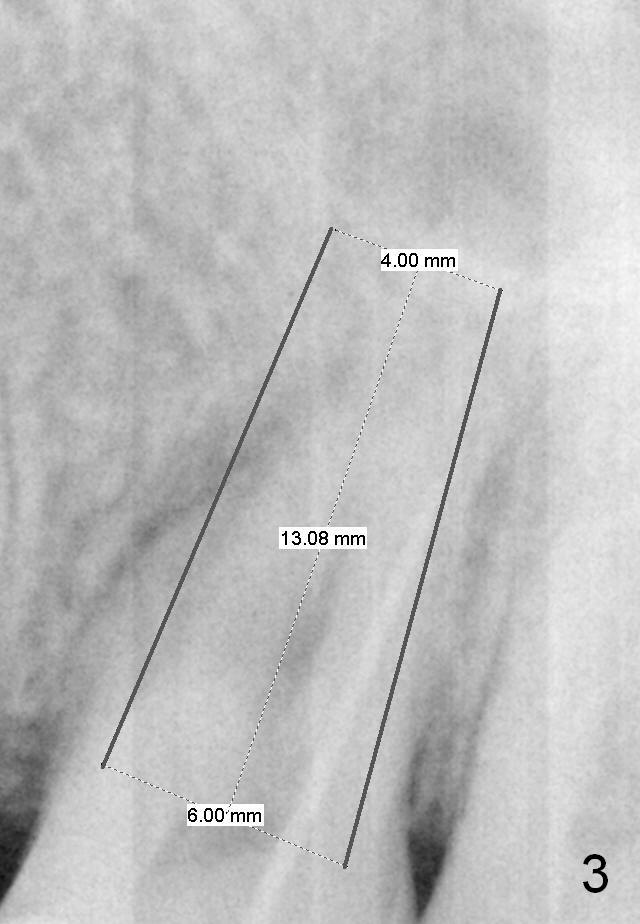

A 46-year-old woman has apical periodontitis with distal crack line at #14. There are 2 fistulae (buccal and palatal). A gutta percha is inserted into the buccal one (Fig.1 <). After extraction and Xylocaine gauze application in the socket, use 1.6 mm pilot drill in the septum for 7 mm, followed by Magic split and expanders for sinus lift. Place a relatively small implant (IBS, 4.5x13 or 5x11 mm, Fig.2) in the septum or a large one (6x13 mm or 6 mm 1-piece one, Fig.3) to obliterate the whole socket.